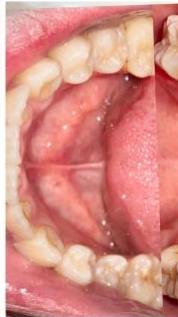

### b) Intraoral Examination

Intraoral examination revealed severe proclination and protrusion of both the maxillary and mandibular incisors [6]. The occlusal relationship was Class I at the canine (tooth 3) and first molar (tooth 6) levels bilaterally. A critical unfavorable biological factor was the proximity of the mandibular incisor roots to the labial cortical plate, representing a high-risk condition when planning extraction-based anterior retraction mechanics [10-12]. All four third molars were present.

Figure 2: Pre-Treatment Intraoral Photographs